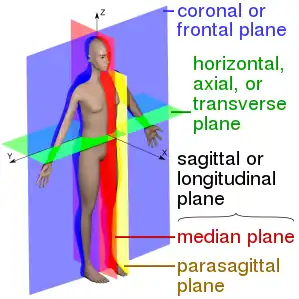

Planes

Anatomical terms describe structures with relation to four main anatomical planes:[2]

- The median plane, which divides the body into left and right.[2][6] This passes through the head, spinal cord, navel, and, in many animals, the tail.[6]

- The sagittal planes, which are parallel to the median plane.[1]

- The frontal plane, also called the coronal plane, which divides the body into front and back.[2]

- The horizontal plane, also known as the transverse plane, which is perpendicular to the other two planes.[2] In a human, this plane is parallel to the ground; in a quadruped, this divides the animal into anterior and posterior sections.[3]